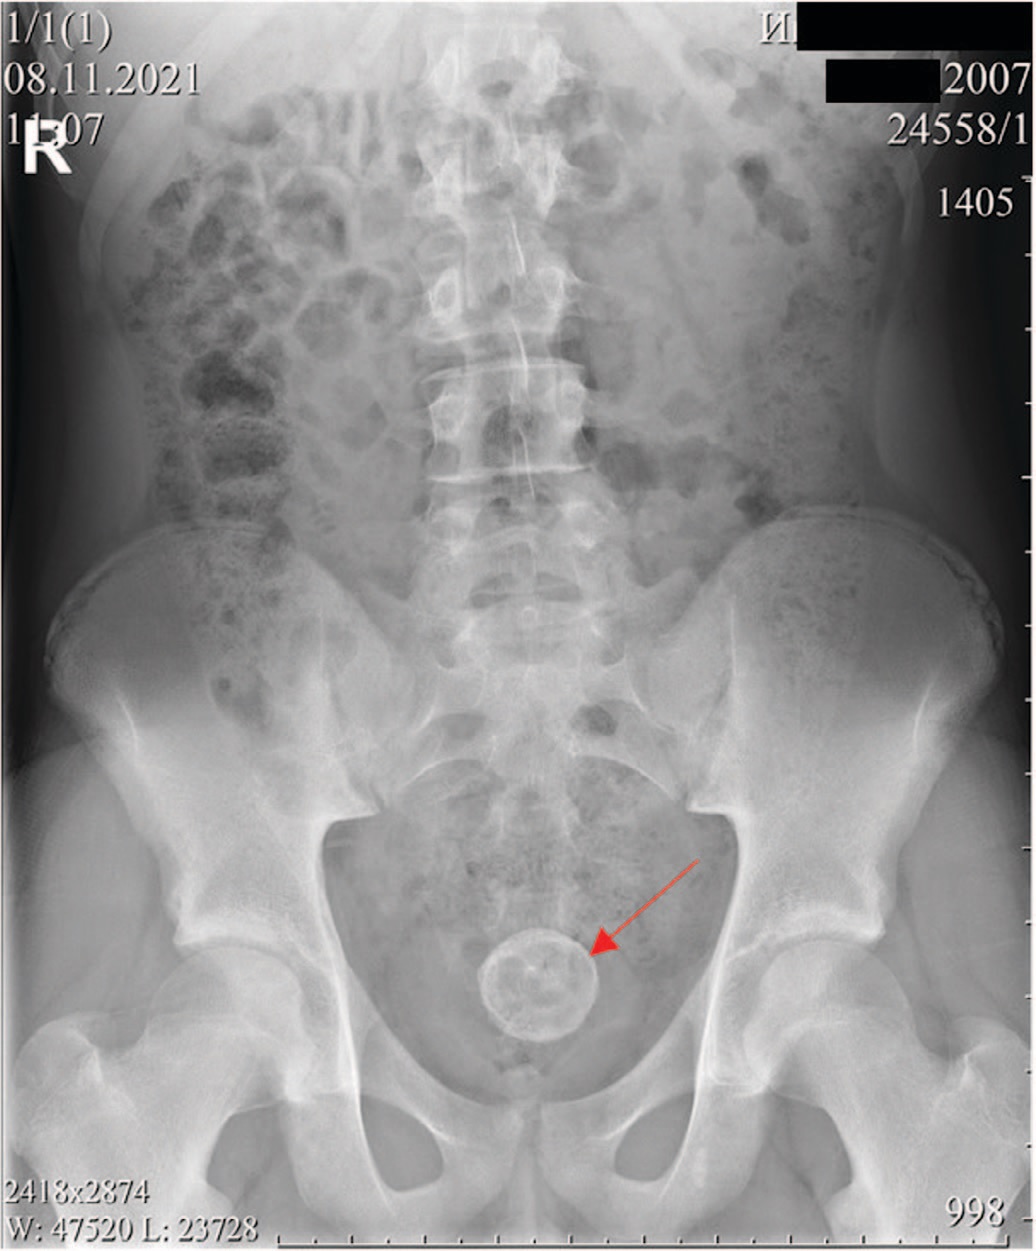

Изображения КТ конкрементов мочевого пузыря